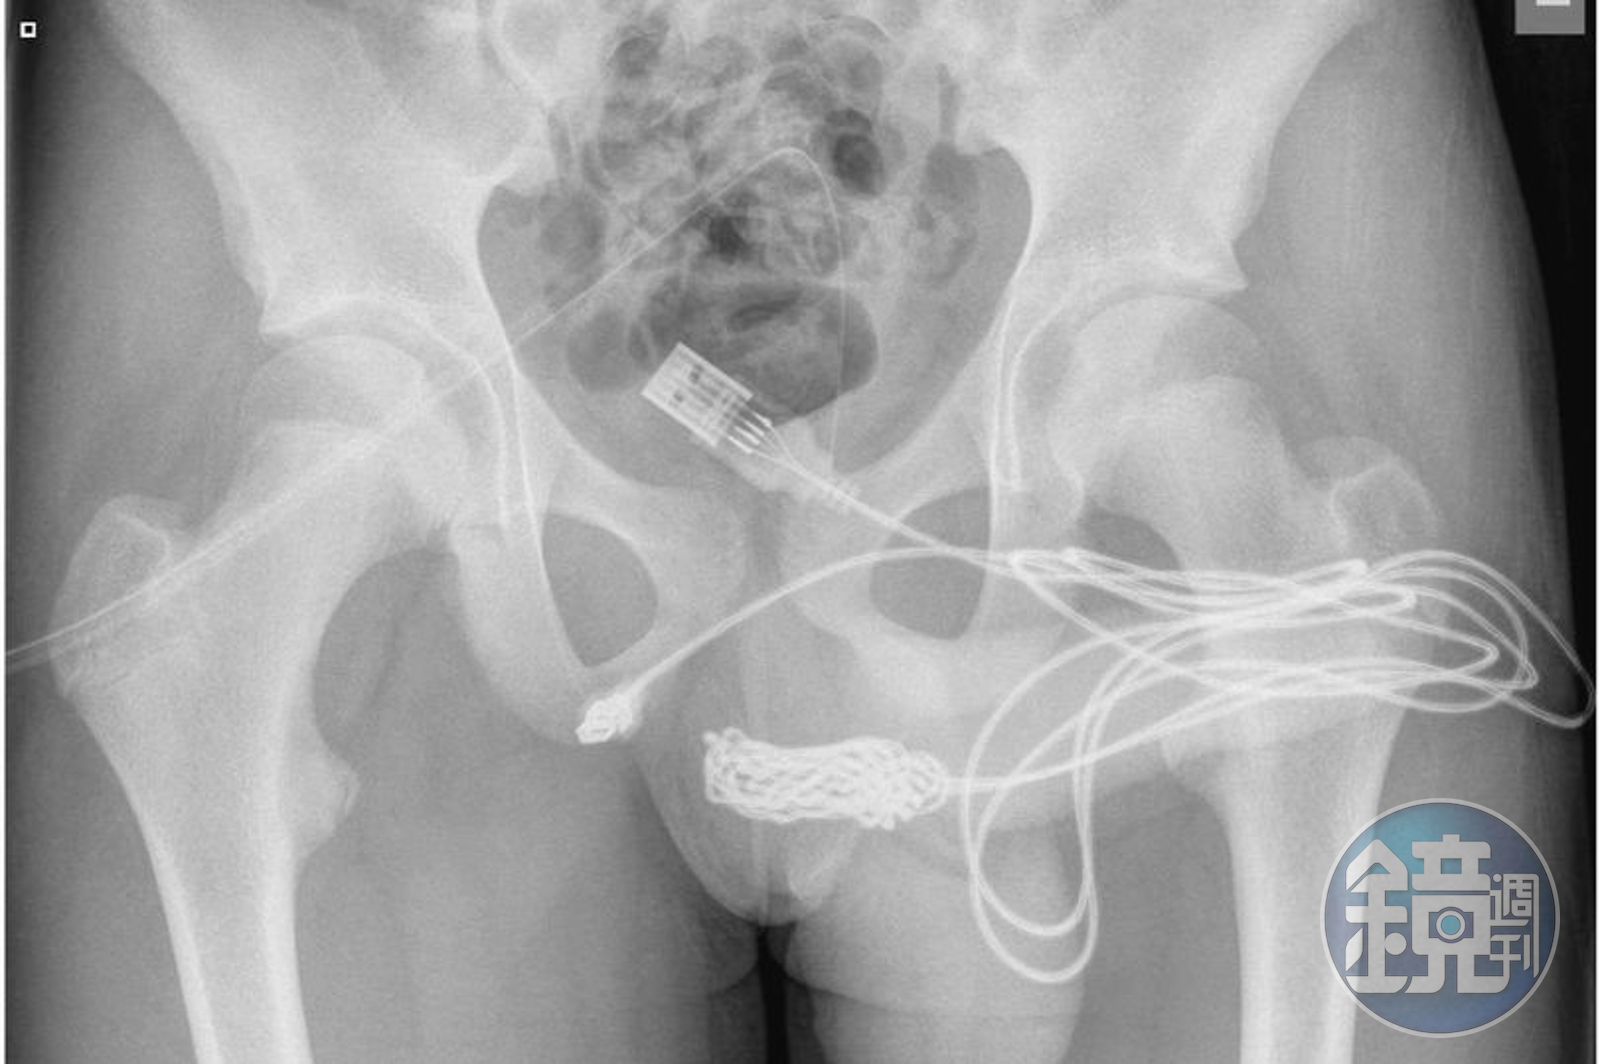

醫師照X光發現,不僅體內有明顯的USB傳輸線影像,整條線甚至打結,糾結在一起。最後少年被轉往倫敦大學醫學院進行手術,醫師將少年的生殖器周圍肌肉切開,並逐步把傳輸線打結之處切除,最後成功將傳輸線取出。